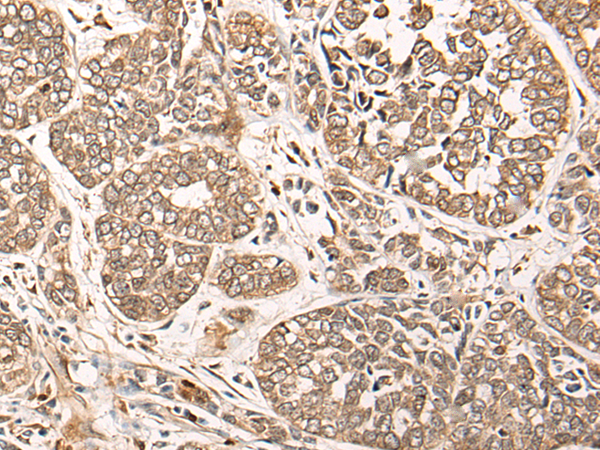

Applications: |

ELISA, IHC |

IHC positive control: |

Human esophagus cancer |

IHC Recommend dilution: |

50-300 |